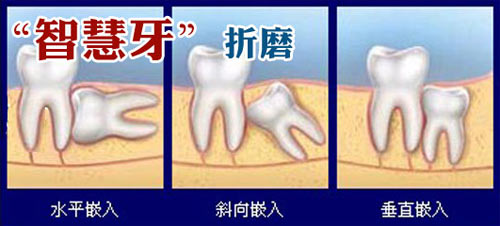

阻生齿生长情况示意图

如果位置长得不好,建议拔除,因为,不良的智齿将在以后的生活中给你带来一些不便。由于其位置靠里,刷牙难清洁到位,易引起龋齿(俗称蛀牙)、牙周炎、牙髓炎等;且智齿往往由于萌发空间不足出现胀痛,还会侵犯邻牙,造成牙疼。如果要拔掉智齿,一定要找专业牙医,进行科学的拍片检查再进行。>>>拔一颗智齿多少钱?点击问答

1.龋齿(蛀牙)造成邻牙病变或引发冠周炎。

2.无成对咬牙、智齿阻生或引起其他病变。

4.因阻生疑为不明原因的神经痛病因者,或可疑为病灶牙时,亦应拔除。